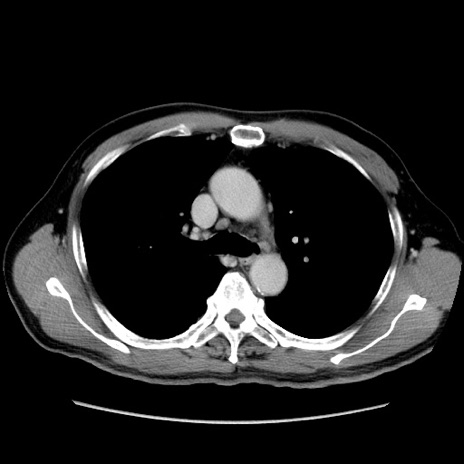

冠状断像

【症例】60歳代 男性

【主訴】右鼠径部膨隆

【現病歴】1年程前より右鼠径部膨隆あり。自己にて還納可能だったため放置していた。3時間前より右鼠径部の脱出を認め、還納困難となり受診。

【既往歴】高血圧

【身体所見】右鼠径部に小児頭大の膨隆あり。弾性硬であり、用手還納は困難。左鼠径部にも膨隆を認める。脱出はなし。

【データ】WBC 15500、CRP 測定なし